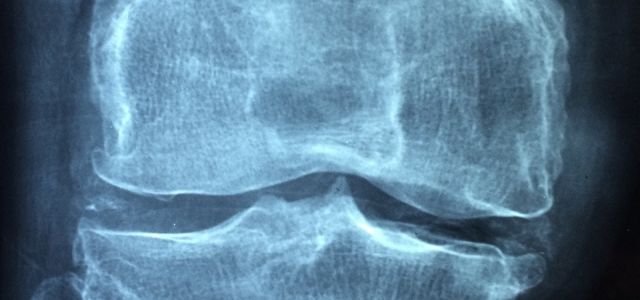

Artrose daarentegen is een degeneratieve gewrichtsaandoening die vooral geassocieerd wordt met slijtage van het kraakbeen in de gewrichten. Kraakbeen is het gladde weefsel dat de uiteinden van de botten bedekt en zorgt voor soepele beweging van de gewrichten. Bij artrose raakt het kraakbeen beschadigd en wordt het dunner, waardoor het bot directer met elkaar in contact komt en het gewricht minder goed kan functioneren. Artrose veroorzaakt meestal pijn, stijfheid, verminderde beweeglijkheid en mogelijke zwelling van de aangedane gewrichten. Het komt vaak voor in gewrichten zoals de knieën, heupen, handen en wervelkolom.

Deze aandoening komt vaker voor dan welke andere vorm van artritis dan ook. Het is het gevolg van de "slijtage" die optreedt wanneer je gewrichten te zwaar worden belast. Het komt meestal voor bij het ouder worden, maar kan ook het gevolg zijn van gewrichtsblessures of obesitas, wat extra druk op de gewrichten legt.

Wat er gebeurt: Je verliest de schokdemper van je lichaam. Het kraakbeen, het gladde materiaal dat de uiteinden van botten bedekt, breekt geleidelijk af.

Een voorbeeld is wat er met je knieën kan gebeuren als je overgewicht hebt. De extra kilo's zetten meer druk op het kraakbeen terwijl het wordt samengeperst tussen de botten. Hierdoor raakt het beschadigd en slijt het, waardoor er minder overblijft om het gewricht te beschermen.

Het beschadigde kraakbeen veroorzaakt pijn bij beweging. Je kunt een knarsend geluid horen wanneer het ruwe kraakbeenoppervlak van de botten tegen elkaar wrijft. Je kunt pijnlijke uitsteeksels of bulten op het einde van de botten krijgen, vooral aan de vingers en voeten. Ontsteking van het gewrichtsvlies komt niet vaak voor bij artrose.